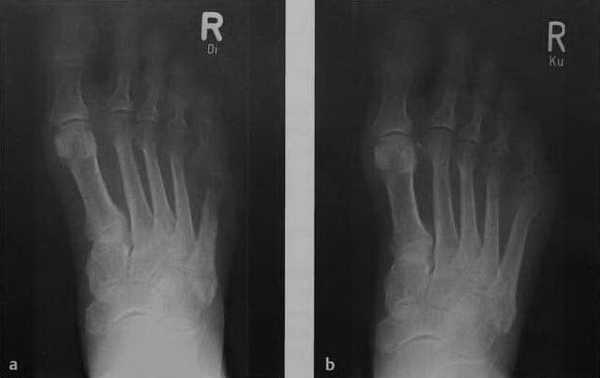

Рентгенологическое изображение острого остеомиелита у пациента с сахарным диабетом: a) Остеолитическая деструкция без четких границ в дистальной части диафиза пятой плюсневой кости и плюсне-фалангового сустава. Выраженная остеопения и незначительная реакция надкостницы; b)Рентгенологическое исследование за 3 нед. до этого демонстрирует только припухлость мягких тканей.